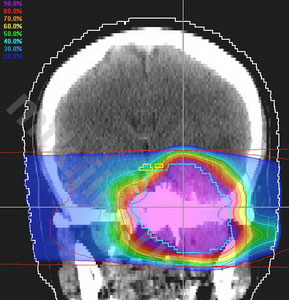

Пример лечения

План конформной протонной лучевой терапии большой (132.5 см3) менингиомы средней черепной ямки (слева), МРТ с контрастом до лечения в середине и МРТ через 12 мес после лечения (справа) – заметное уменьшение опухоли.